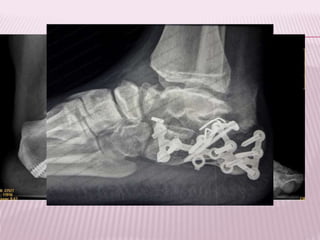

Radiografía de una fractura de tobillo tratada

quirúrgicamente con placa y tornillos de

titanio.

Osteosíntesis: Produce un alto grado de

estabilidad mecánica.